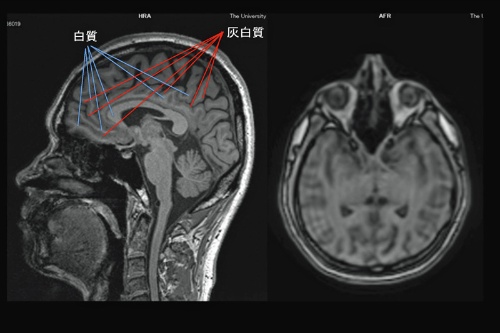

図1.jpg